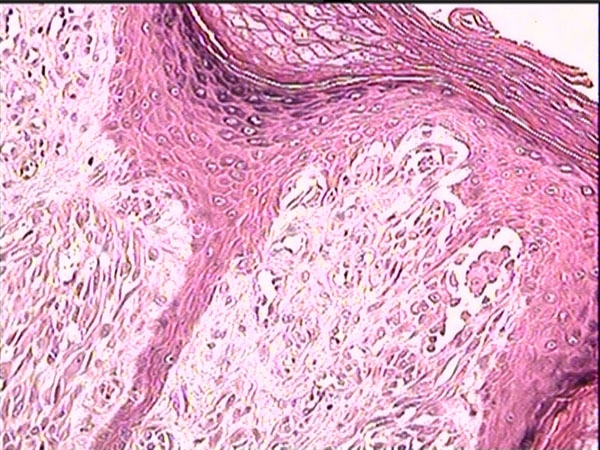

The histopathological examination revealed a tumor composed of mixed epithelioid and spindle cells as nests and small clusters. Now, making the diagnosis is much easier!

Diagnosis: Spitz Nevus

The classic Spitz nevus is predominantly compound, although junctional and intradermal lesions are also observed. The sine qua non of the diagnosis is the presence of large and/or spindle-shaped melanocytes, usually in nests. The nests are composed of an admixture of spindle cells and/or epithelioid cells, although frequently, the spindle-shaped cells predominate.

The spindle cells are usually observed in a fascicular arrangement. These cells have abundant cytoplasm and contain a vesicular nucleus with a conspicuous nucleolus. The epithelioid cells are bizarrely shaped, show poor cohesion, often have several nuclei, and frequently have multiple large nucleoli.

Striking symmetry, sharp lateral demarcation, absent (or rare) mitoses, absence of atypical mitoses, presence of eosinophilic and periodic acid-Schiff (PAS)–positive globules (Kamino bodies) and nondisruptive (single-file like) infiltration of collagen are important features indicating the diagnosis of Spitz nevi. Single-file melanocytes may also be observed in the reticular dermis located at the base of the lesion (dispersion).

Another important feature is the maturation of cellular elements toward the dermis. Pagetoid spread of the melanocytes is usually confined to the center of the lesion; when present, it can cause confusion with melanoma.

The epidermis is hyperkeratotic and acanthotic. A cleavage artifact of fixation is commonly noticed above the nests and around superficial dermal elements.